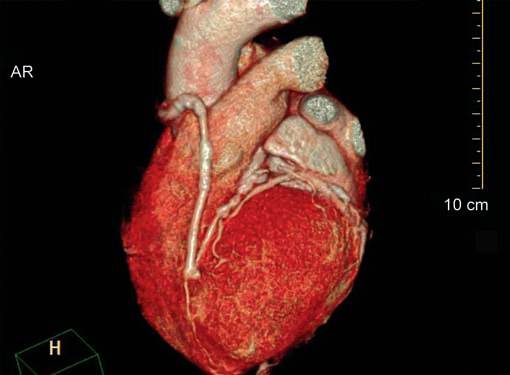

CT is the preferred tool of investigation of coronary bypass grafts (Fig. 9). Reversed saphenous vein grafts (SVGs) are optimally studied consistently. Anastomotic sites are studied effectively. However, distal anastomosis of venous graft to obtuse marginal branch (OM) is relatively difficult to evaluate because of diminishing caliber of native vessel. Arterial grafts pose a small challenge due to artifacts of associated surgical clips (Figs 10A and B). Ostium and proximal part of graft are assessed well. However, distal anastomotic site may be difficult to assess on occasions. RIMA graft, posterior descending artery (PDA) graft, gastroepiploic artery graft can also be studied. Stenosed venous grafts

can be stented and the same can be evaluated by CT (Fig. 11). Like native RCA, RCA grafts (Figs 12A and B) are more susceptible to motion artifacts when compared to LAD and OM grafts. Catheter angiogram can be used to answer specific queries after CT angiogram.